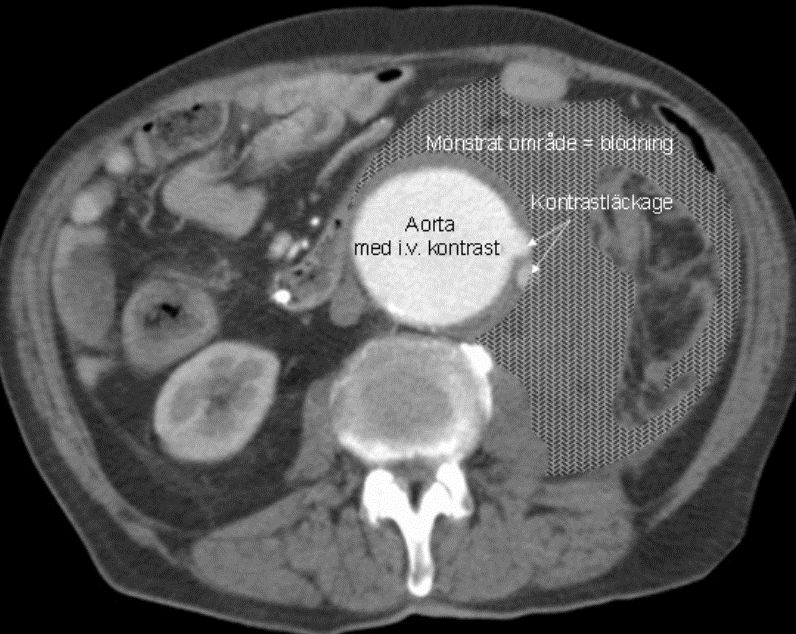

Q

Vad ser du på bilden?

A

• Bukaortaaneurysm med stort vänstersidigt hematom och pågående blödning retroperitonalt.